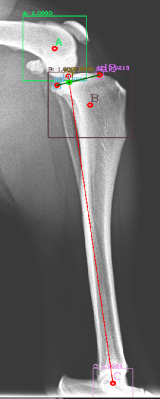

Following the identification of points of interests, and drawing of the lines of interest, i.e. the Functional Tibial Line (FTL) and the Medial Tibial Plateau Line (MTPL), another line is drawn such that the relation of new line and the FTL is 90°. Tibial plateau angle is the angle between this new line and the MTPL; this is shown in Fig. 3.

Most of the source dataset of over a thousand unique knee radiographs were distorted, had poor patient positioning, or were otherwise unfit for annotating. 250 of the original images were of sufficient quality to contribute to this effort. These images were set to have 6 different classes for training purposes, as mentioned and shown in Fig. 4. These were then trained using YOLOv3 [10] and the results of the predicted annotations are shown in Table I. From these predictions the centroids were extracted, which is then used to plot the FTL and MTPL. Then using the method mentioned in Section II, TPA is calculated. Examples of images, the region of interests detection and their respective TPA determination is shown in Fig. 6 and Table I: